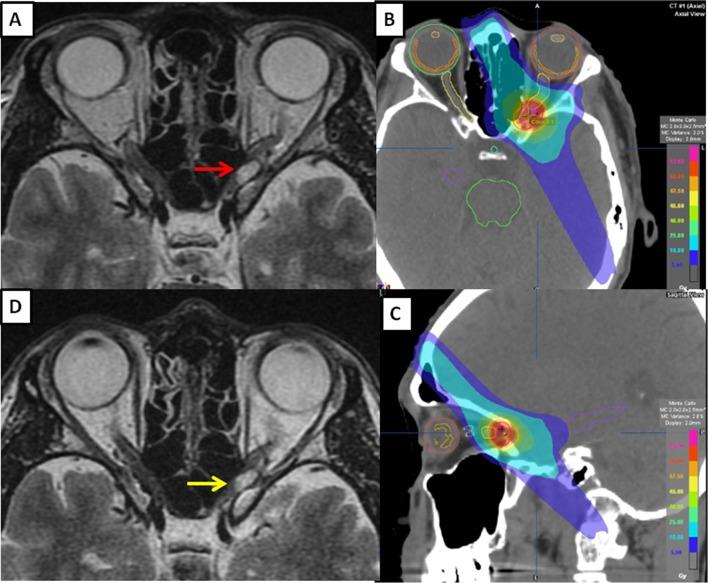

During precision radiotherapy to treat optic nerve sheath meningioma, early improvement in visual function has been seen. This has been difficult to explain biologically. In the present study, we aimed to investigate this rapid improvement in visual function. To this end, we prospectively tested a single patient's visual field (VF) using Humphrey automated perimetry at weekly intervals. The patient exhibited significant stepwise improvement in VF during an intensity-modulated radiotherapy course.

在对视神经鞘膜瘤进行精确放射治疗期间,已观察到视觉功能的早期改善。从生物学角度很难解释这一现象。在本研究中,我们旨在探究视觉功能的这种快速改善情况。为此,我们前瞻性地每周使用汉弗莱自动视野计对一名患者的视野(VF)进行检测。在调强放射治疗过程中,该患者的视野出现了显著的逐步改善。